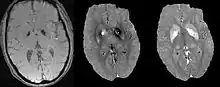

Differentiating calcification from iron

It has been confirmed in in vivo and phantom experiments that cortical bones, whose major composition is calcification, are diamagnetic compared to water.[11][18] Therefore, it is possible to use this diamagnetism to differentiate calcifications from iron deposits that usually demonstrate strong paramagnetism.[19] This may allow QSM to serve as a problem solving tool for the diagnosis of confounding hypointense findings on T2* weighted images.